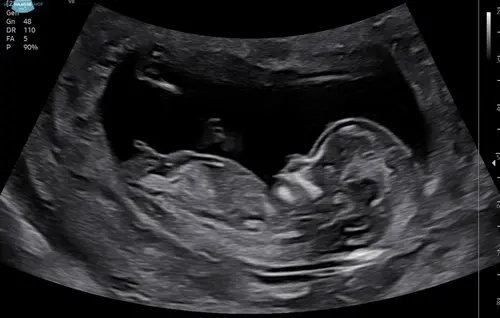

Iemand die hier iets uit kan halen? Ik zie het zelf niet..

Nog maar een keer. Niemand die iets ziet? Ook als jullie het niet kunnen zien is het wel fijn als iemand reageert want nu zie ik dat er op veel niet gereageerd wordt en het is onduidelijk waarom niet 🙊🙊

Meisje

Ik kan het niet goed zien helaas!